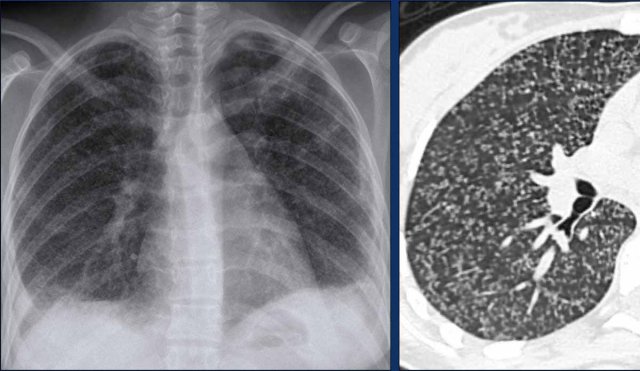

Miliary disease

This is the result of hematogenous spread of TB to other organs.

In the lung it manifests as multiple 2-3 mm nodules with a random distribution.

These nodule can be difficult to appreciate on a chest x-ray, but are well seen on a chest CT.

It is an uncommon finding, but with a high specificity.